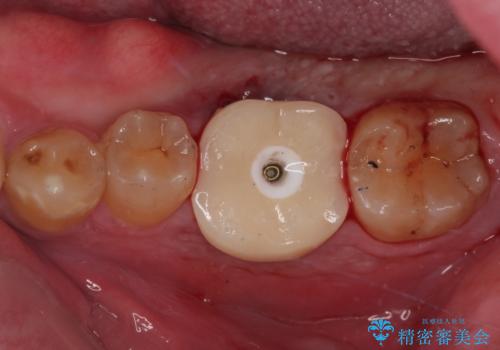

咬合力で破折した奥歯 抜歯即時埋入インプラントによる補綴治療

- 食事中に奥歯が痛むとのことで来院された患者様です。

レントゲンやCTより、深くまで破折していることが分かり、抜歯が必要な状態でした。

歯槽骨の状態は良好であったため、抜歯即時埋入インプラントによる補綴治療を行うこととしました。

インプラント埋入時に植立具合の安定性を測定したところ、十分な数値が得られたため、速やかに仮歯を装着して咬合回復をさせることができました。

抜歯を含めた外科処置を1回に抑えることができ、あっという間に治療を終えることができました。